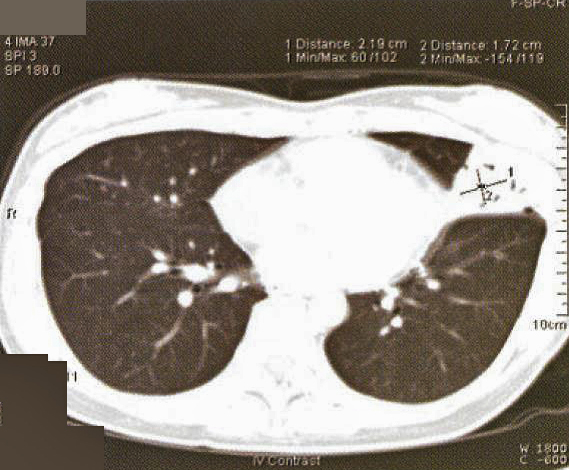

Fig. 1: CXR taken at presentation (a) and 17 days later (b). Left mid zone opacity remained unchanged despite a course of Azithromycin Blood tests revealed normal CBP, ESR & routine biochemistry. Antibodies for HIV 1 & 2 were negative. Thyroid function was normal but thyroid peroxidase antibody was elevated at 81.7 IV/ml (normal <12). CT thorax showed an area of segmental consolidation in the lingular segment of left upper lobe (fig. 2a), with no abnormality detected in other parts of the lungs, mediastinum or body structures. Bronchoscopy revealed nothing abnormal and bronchial washings grew alpha streptococcus but were negative for AFB smear, M tuberculosis DNA or malignant cells. She developed a cough after the bronchoscopy and responded to a course of levofloxacin.

She was treated with chemotherapy – 3-weekly regime of cyclophosphamide, adriamycin, vincristine & prednisolone (CHOP) – and tolerated the treatment well. A CT thorax was performed after 3 cycles of chemotherapy showed a slight reduction in the area of consolidation (fig. 2b).